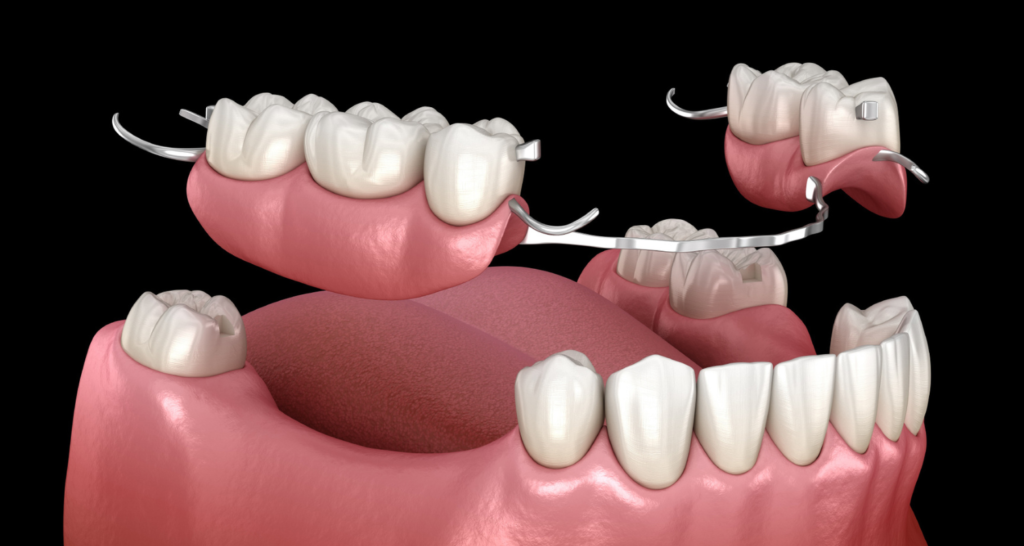

Une prothèse amovible, également appelée dentier ou appareil dentaire amovible, est un dispositif utilisé pour remplacer les dents manquantes et restaurer la fonction masticatoire et esthétique de la bouche. Il s’agit d’une prothèse dentaire qui peut être retirée et remise en place par le patient lui-même. Il est important de consulter un dentiste ou un prothésiste dentaire qualifié pour la conception, la fabrication et l’ajustement appropriés d’une prothèse amovible, afin de garantir un bon ajustement, une fonction masticatoire adéquate et un aspect esthétique satisfaisant.

Une prothèse amovible, également appelée dentier ou appareil dentaire amovible, est un dispositif utilisé pour remplacer les dents manquantes et restaurer la fonction masticatoire et esthétique de la bouche. Il s’agit d’une prothèse dentaire qui peut être retirée et remise en place par le patient lui-même. Il est important de consulter un dentiste ou un prothésiste dentaire qualifié pour la conception, la fabrication et l’ajustement appropriés d’une prothèse amovible, afin de garantir un bon ajustement, une fonction masticatoire adéquate et un aspect esthétique satisfaisant.